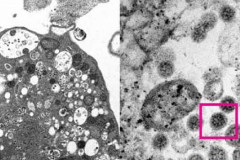

В Армении за сутки зарегистрирован 621 новый случай заражения коронавирусом Курильщики сталкиваются с повышенным риском тяжелого течения COVID-19 – исследов... СМИ: Авиасообщение между Турцией и Арменией начнется 2 февраля У переболевших COVID-19 людей обнаружили следы повреждения мозга COVID-19 может поражать мозг сильнее болезни Альцгеймера – исследование В Армении за сутки зарегистрировано 360 новых случаев заражения коронавирусом Погода в Армении: ночные морозы временно ослабеют Как долго омикрон-штамм может «выживать» на различных поверхностях? В Матагисе обнаружены останки еще одного участника войны Почему после COVID-19 вкус еды пропадает или меняется? В Армении вновь объявлены сборы резервистов Крупная и цепная авария на автодороге Ереван-Аштарак: есть пострадавший В одном из пивных баров Еревана произошла стрельба, ранена женщина ДТП в Ширакской области: Есть пострадавший Погода в Армении Погода в Армении Пандемия коронавируса вызвала рост смертности от сердечно-сосудистых заболеваний... Почему одни люди много раз заражаются коронавирусом, а другие не болели ни разу? В аварии в Арагацотнской области погибли супруги Коронавирус в Грузии: 2 622 новых случая заражения, 28 человек скончались Коронавирус в Армении: 4 новые смерти Погода в Армении ААЦ отмечает праздник Рождества и Богоявления В Армении за сутки зарегистрировано 134 новых случая заражения коронавирусом Пенсионерам на заметку: Выплата пенсий с 1 января осуществляется безналично В 2029 году к Земле подлетит критически опасный астероид В Ереване на площади обнаружен труп мужчины Крупное ДТП в селе Вохджаберд Котайкской области: есть пострадавший В Армении за сутки зарегистрировано 88 новых случаев заражения коронавирусом ВОЗ: Омикрон по-прежнему представляет собой «очень высокий» риск